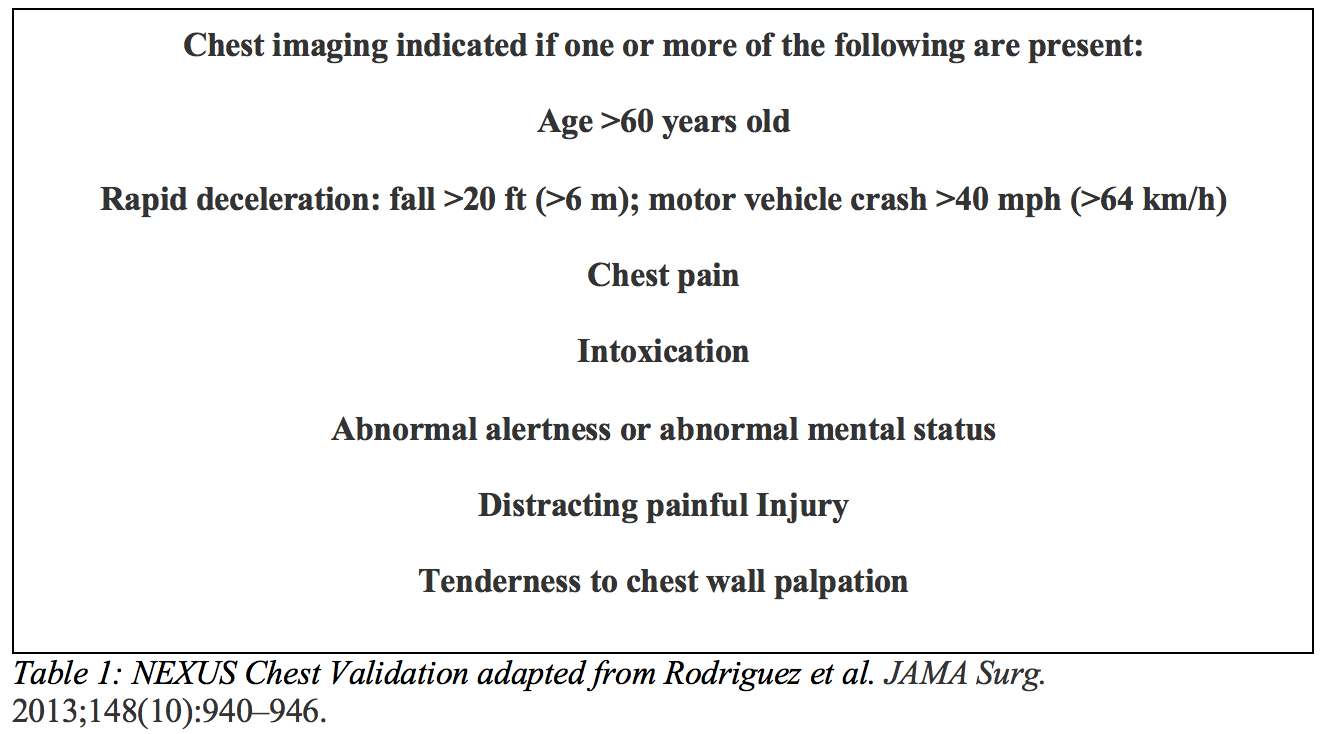

Similar to the National Emergency X-Radiography Utilization Study (NEXUS) Criteria, a NEXUS Chest Rule has been developed to help limit overutilization of imaging and radiation exposure in blunt trauma patients. A cohort study prospectively validated this decision instrument and found it to have a 98% sensitivity for predicting clinically significant intrathoracic injury in blunt trauma patients over the age of 14 years old.20 However, the criteria should only supplement clinical gestalt and decision making, rather than replace it.